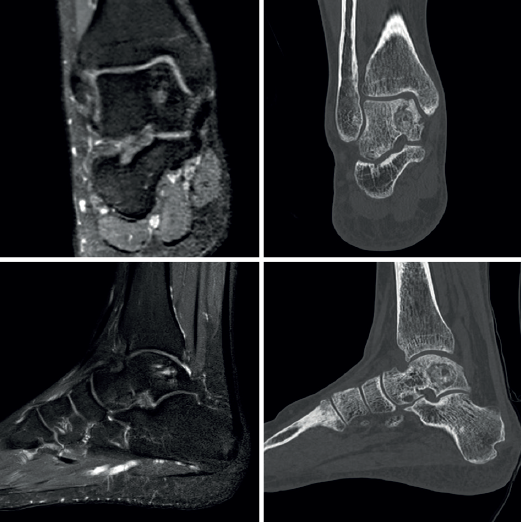

El paciente inicia la movilización activa y pasiva supervisado por un fisioterapeuta a la tercera semana. Realiza descarga por espacio de 6 semanas, seguida de carga parcial progresiva según la tolerancia. Presenta mejoría del control del dolor respecto a la situación preoperatoria (EVA: 8 → 1) y mejoría en la escala funcional (AOFAS: 59 → 90) tras 4 meses de tratamiento. Se realizan controles radiográficos a la cuarta y la décima semana de la intervención. Se realiza estudio por TAC a los 4 meses y al año de la intervención. Se realiza estudio por RM al año de la intervención quirúrgica. Los controles radiológicos muestran preservación de la superficie articular tibioastragalina y relleno de la cavidad quística (Figuras 7 y 8).

Tras 15 meses de seguimiento, el paciente permanece asintomático, con un rango de movilidad completo, realizando trabajos de carga y practicando deportes de carrera, salto e impacto de forma recreativa (Figura 9).